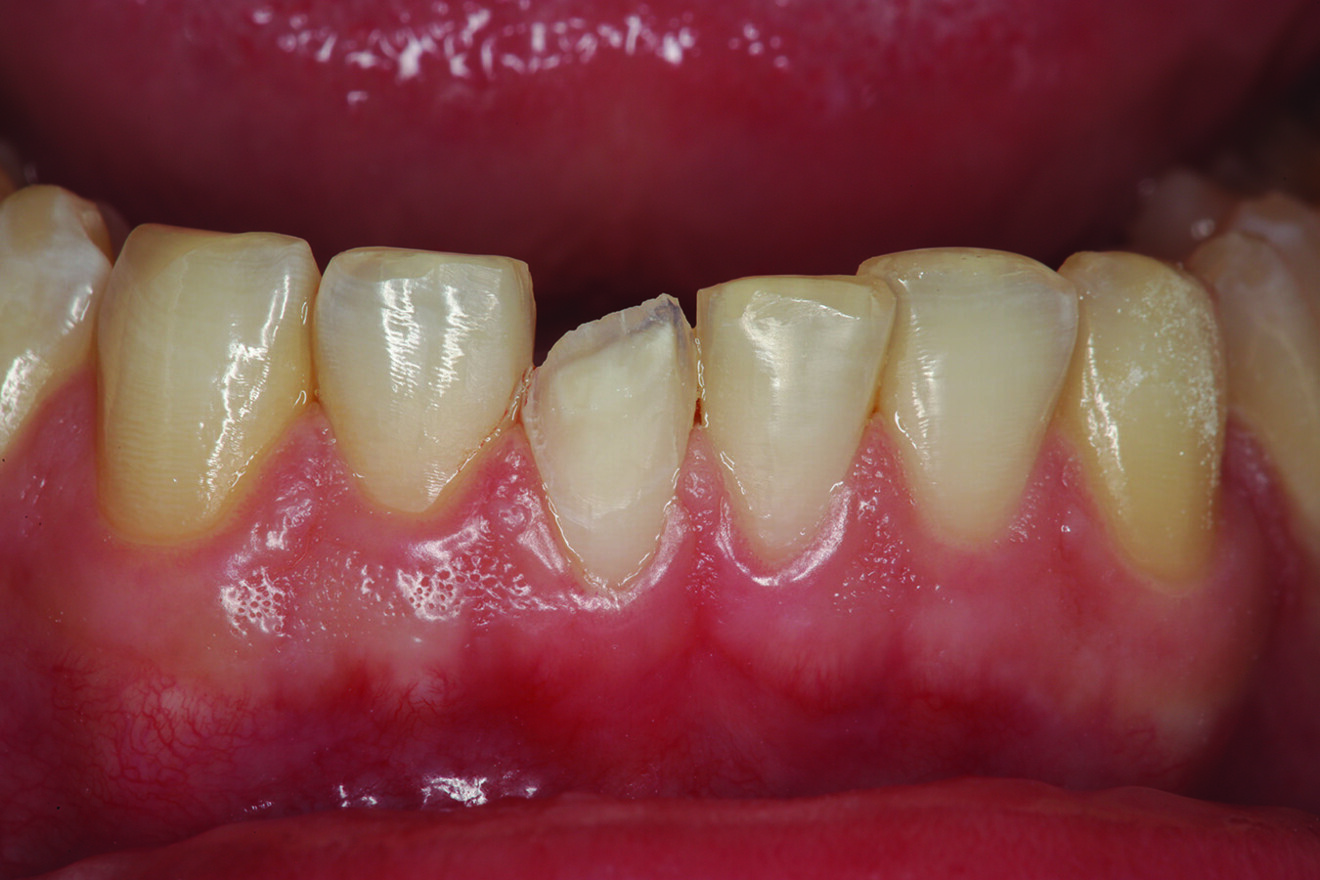

Fig. 1: Pre-op retracted facial view of the fractured composite restoration on tooth #11 with the teeth in maximum intercuspation. (All images: Robert A. Lowe)

The patient presented with a fractured Class IV mesial–incisal composite restoration on tooth #11 (Fig. 1). It had been repaired three times dur­ing the past year and had fractured again. Was this due to poor technique, maybe inferior materials? More than likely, it was due to occlusion. Aside from the amount of composite on the facial sur­face that extended beyond the fractured area, most of the palatal surface of the tooth was worn through to the dentine due to hyperfunction in protrusive and lateral excursion over many years, creating a functional and aes­thetic dilemma for the patient. A “conservative” approach may have been to bond the tooth again with composite and hope for the best. However, this may not have been the best long-term approach considering the functional stress in this area, even with the best tooth alignment. After all, how conservative is it to continually assault the tooth with rotary instrumentation to keep fixing a composite that continues to fracture?